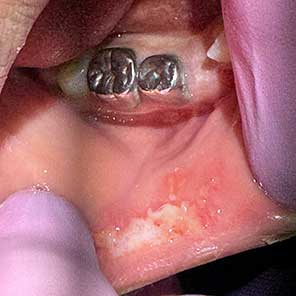

If your child bites his or her cheek, tongue or lip, there may be swelling over the next 4-5 days. This is most common in a child under the age of 8. A soft scab may develop that looks like a yellowish white plaque or like a large traumatic ulcer. This is a normal part of the healing process. The lesion should heal over the next 10-14 days.